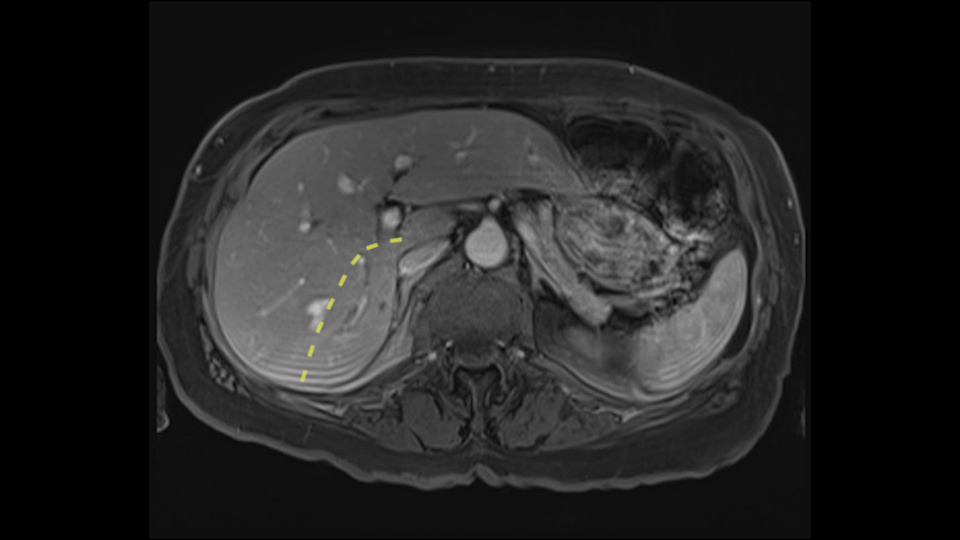

So now we’ve assessed extent of metastatic disease, we’ve got some idea of fitness. The last item and I put it third because it’s actually the easiest of the three is what is the extent of the disease within the liver. For that we use contrast-enhanced magnetic resonance scanning, contrast-enhanced MR good for planning treatment.

I look at this in two ways: first of all, I’m going to make an assessment of the distribution of the lesions and second, I’m going to say what major inflow/outflow structures will I need to deal with in order to resect the tumor. It’s very easy. So distribution of disease, inflow/outflow structures.

So we’re starting down here: right kidney Segment 6, and you can see there is a first lesion there. It’s probably in 5. I can’t say definitively just yet. That’s the lesion at the back it’s probably in Sg6.

Coming up a little bit higher. There’s a little bit of biliary dilatation as well. On the right side of the liver. Which may be nothing but it may be an indicator or harbinger of nodal disease in the hepatoduodenal ligament so something to be aware of. If the enzymatic liver function tests are normal and there’s no evidence of a stone in the common bile duct on cross sectional imaging you wouldn’t need to do anything about it but just to be aware of that.![[RHV]](jpg/preop_as_p4.jpg)

So we’re going through the liver segments now. Here we’ve got the inflow; here’s the main portal vein, right anterior sectoral portal vein, right posterior sectoral portal vein there. Here’s the main here going to the left lobe first of all. So that’s 3 and 2 there, they look clear, and there’s a good size of the left lobe with a good girth. So 3 and 2 look clear. There are usually more feedback branches from the left portal vein to segment 4b but that also looks relatively clear. There’s a little more disease over on the right side there. So that would be...right hepatic vein here...that’s Segment 7. So we’ve got disease in 7, 5, probably in 6 on the right side; at least 3 lesions. That’s the distribution of the lesions.![[Ant. RPV] [Main PV] [Post. RPV]](jpg/preop_as_p5.jpg)

So look at the MR from two points of view, firstly distribution of the lesions, secondly what kind of parenchyma would need to be resected to remove that disease and what kind of operation would we plan. And again so what we’re planning here would probably be a right hepatectomy. We know that there is plenty of disease-free left lobe. Segment 4 looks nice and clear. So a transection line coming down to about that kind of area would clear all of the disease. So that’s the kind of preoperative planning that we’d need to do.